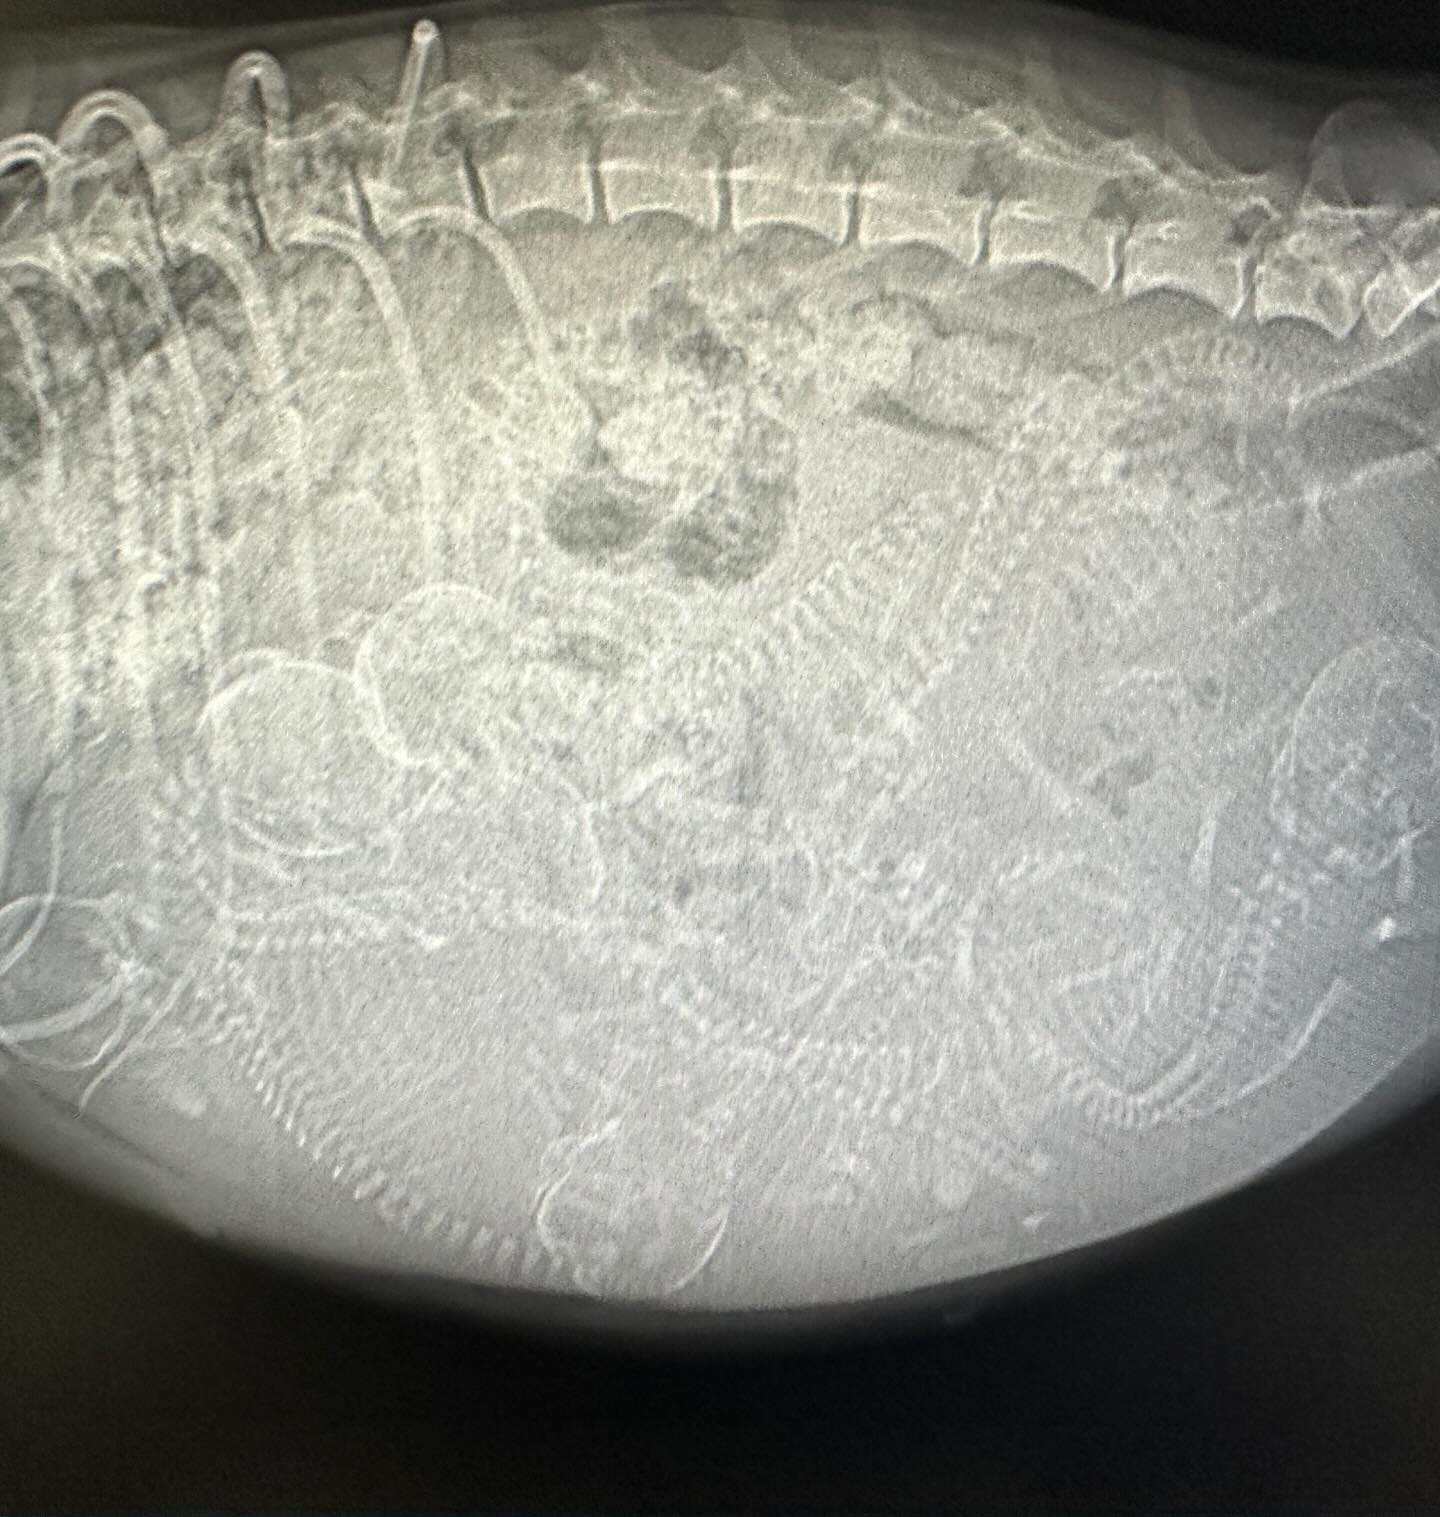

To make sure Pita and her puppies were well cared for, Garcia took Pita to the vet for an ultrasound. The results were astounding. No one expected the small dog to be carrying so many puppies.